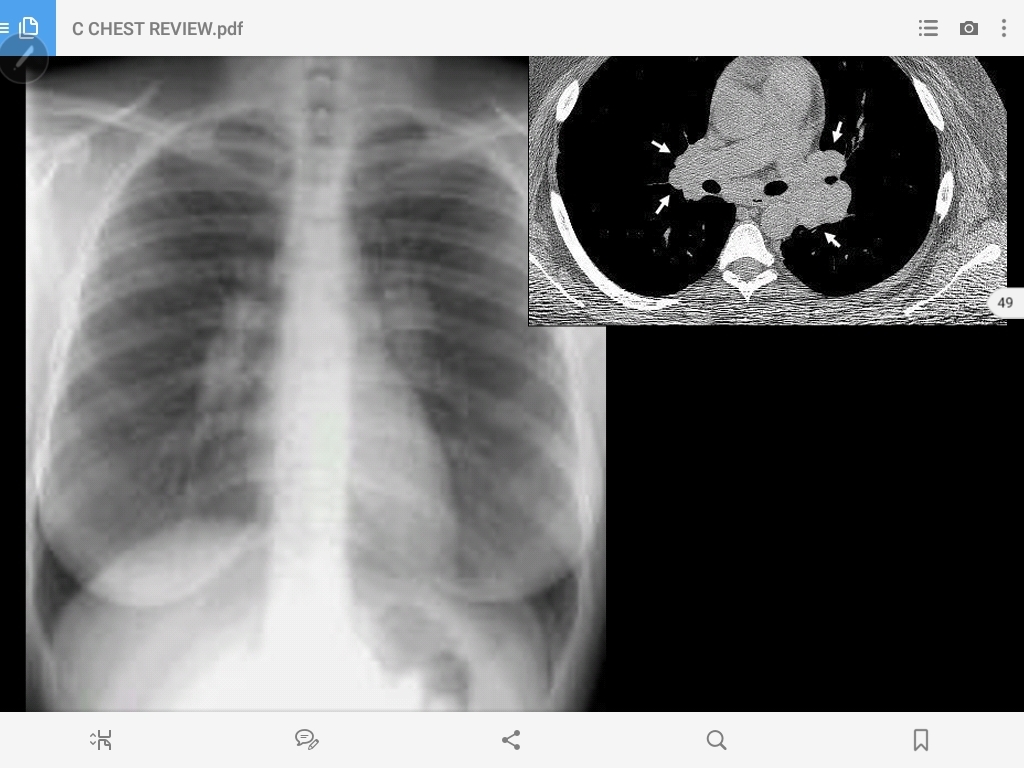

hilar lymph node enlargement and a peripheral granuloma (Ranke complex)